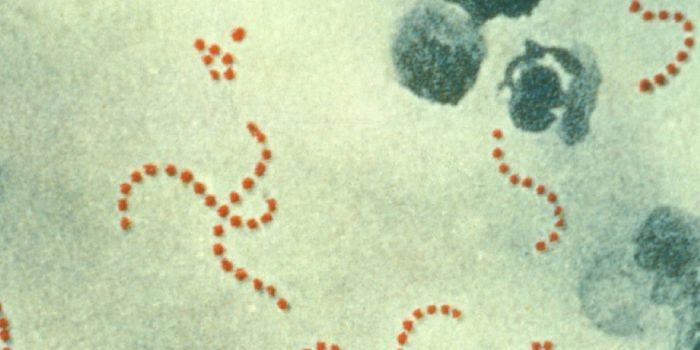

MAR 05, 2023MicrobiologyEstimates vary, but Streptococcus pyogenes infections may be responsible for the deaths of over 500,000 people every yea ...

SEP 12, 2019MicrobiologyStreptococci are a group of Gram-positive microbes that include pathogens that can cause mild and serious infections.